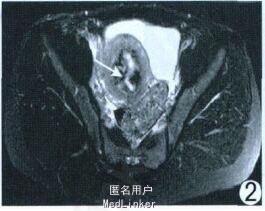

查体:子宫增大如孕8 周。实验室检查:血绒毛膜促性腺激素1.76 mIU/ml 。超声:子宫实性占位, 肌瘤变性。M RI :子宫明显不均匀增大, 宫腔内见约5.13 cm ×4.62 cm 类圆形异常信号, T1WI 呈等低信号, 其内见部分高信号(图1), T2WI 呈低信号, 其内夹杂线状、片状明显高信号(图2);增强后无强化(图3)。M RI 诊断为子宫腔内占位:子宫肌瘤(黏膜下型), 大部分变性。